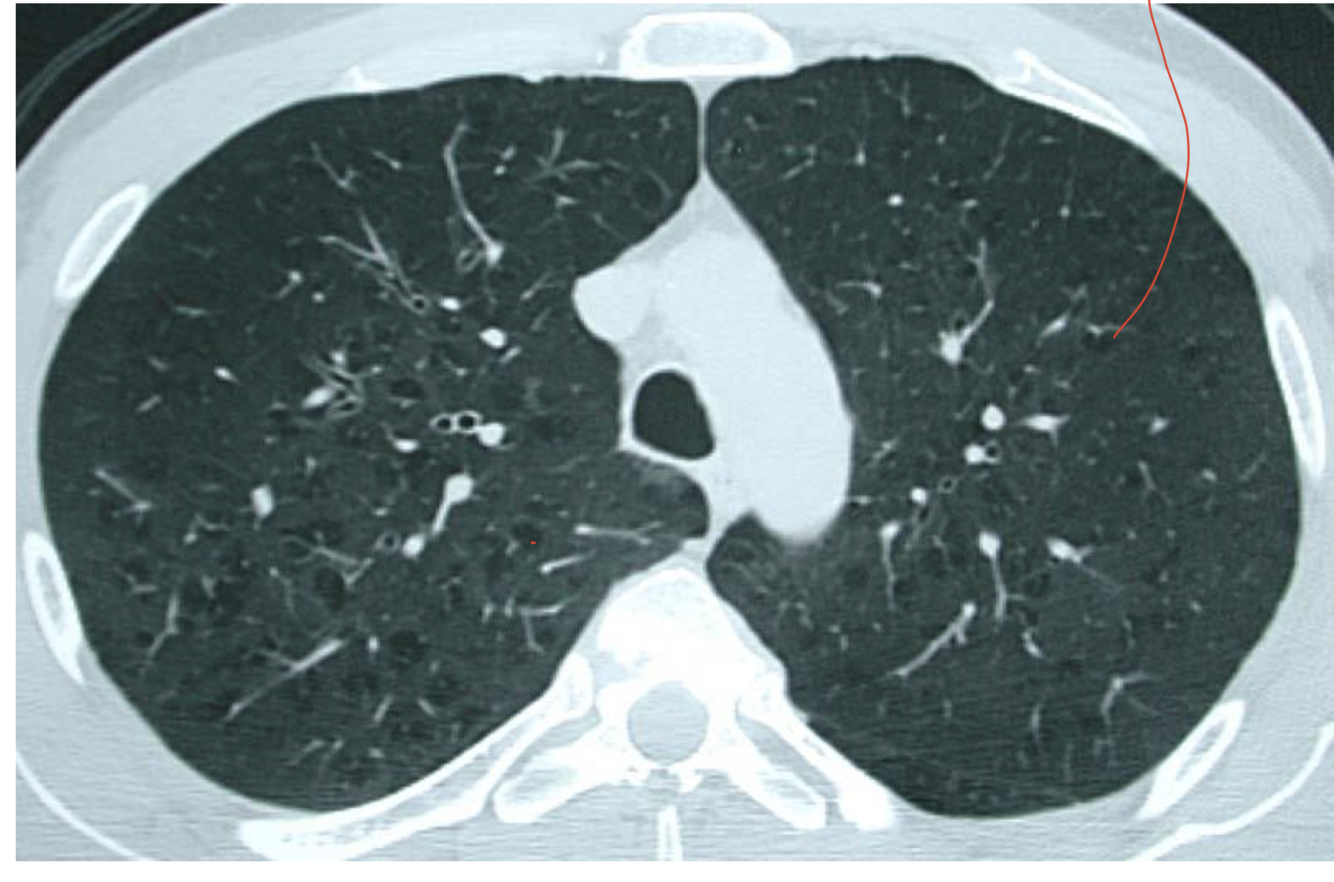

interpret CT scan

there are small little gas trapping asepcts. this is COPD. Emphysematous.